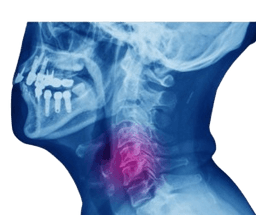

Anterior Cervical Discectomy & Fusion

Anterior cervical discectomy and fusion (ACDF) is a surgical procedure that treats pain caused by compressed nerves in the neck. This surgical approach involves removing the disk between the affected bones and fusing them together. In turn, ACDF surgery moves the pressure on the nerves or spinal cord. This procedure treats the issue in the neck through the front or throat area. Additionally, this procedure also helps in treating different types of arthritis that cause pain. -br ACDF in India surgery removes the pressure from the nerves around the spinal cord. The reason for the pressure is due to bone spurs or bulging disks. Bone spurs form as a result of arthritis. This disc performs as a shock absorber between vertebrae that slips out of place and moves up against a nerve. -br However, ACDF surgery can lead to weakness or damage to the spinal cord. These problems may occur due to accidents or with other serious problems. The pressure on the spinal nerves or spinal cord develops gradually.

Cervical Spine Surgery

Cervical spine surgery is performed to treat problems in the neck such as misalignment, compressed nerves, or spinal cord abnormalities. Some of the most common reasons to perform cervical spine surgery include: